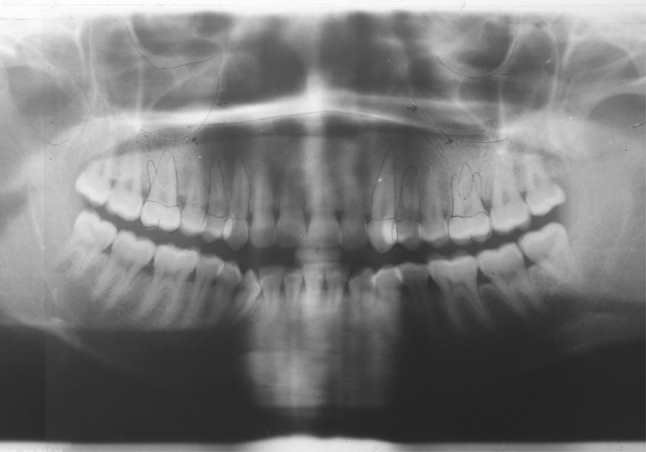

Eight patients (6 females and 2 males) who were advised for fixed orthodontic mechanotherapy with first premolars extraction in maxillary arch and/or both the arches were selected. Sixteen canine distractions (8 on the right side and 8 on the left side) were carried out with a custom made tooth-borne intra oral distraction device. Patients in age group of 14–30 years with moderate to severe crowding, increased overjet or cases with bimaxillary dental protrusion were included in the study and patients with debilitating systemic illness were excluded from the study. Cephalometric and model analysis was done and the maxillary sinus floor was traced (Fig. 1) to assess the proximity of the sinus floor with the canine root apex and surgical planning. It was planned to carry out retraction of canine by periodontal ligament distraction (PLD) on the right side and DAD on the left side under local anesthesia

Fig. 1.

Tracing of maxillary sinus